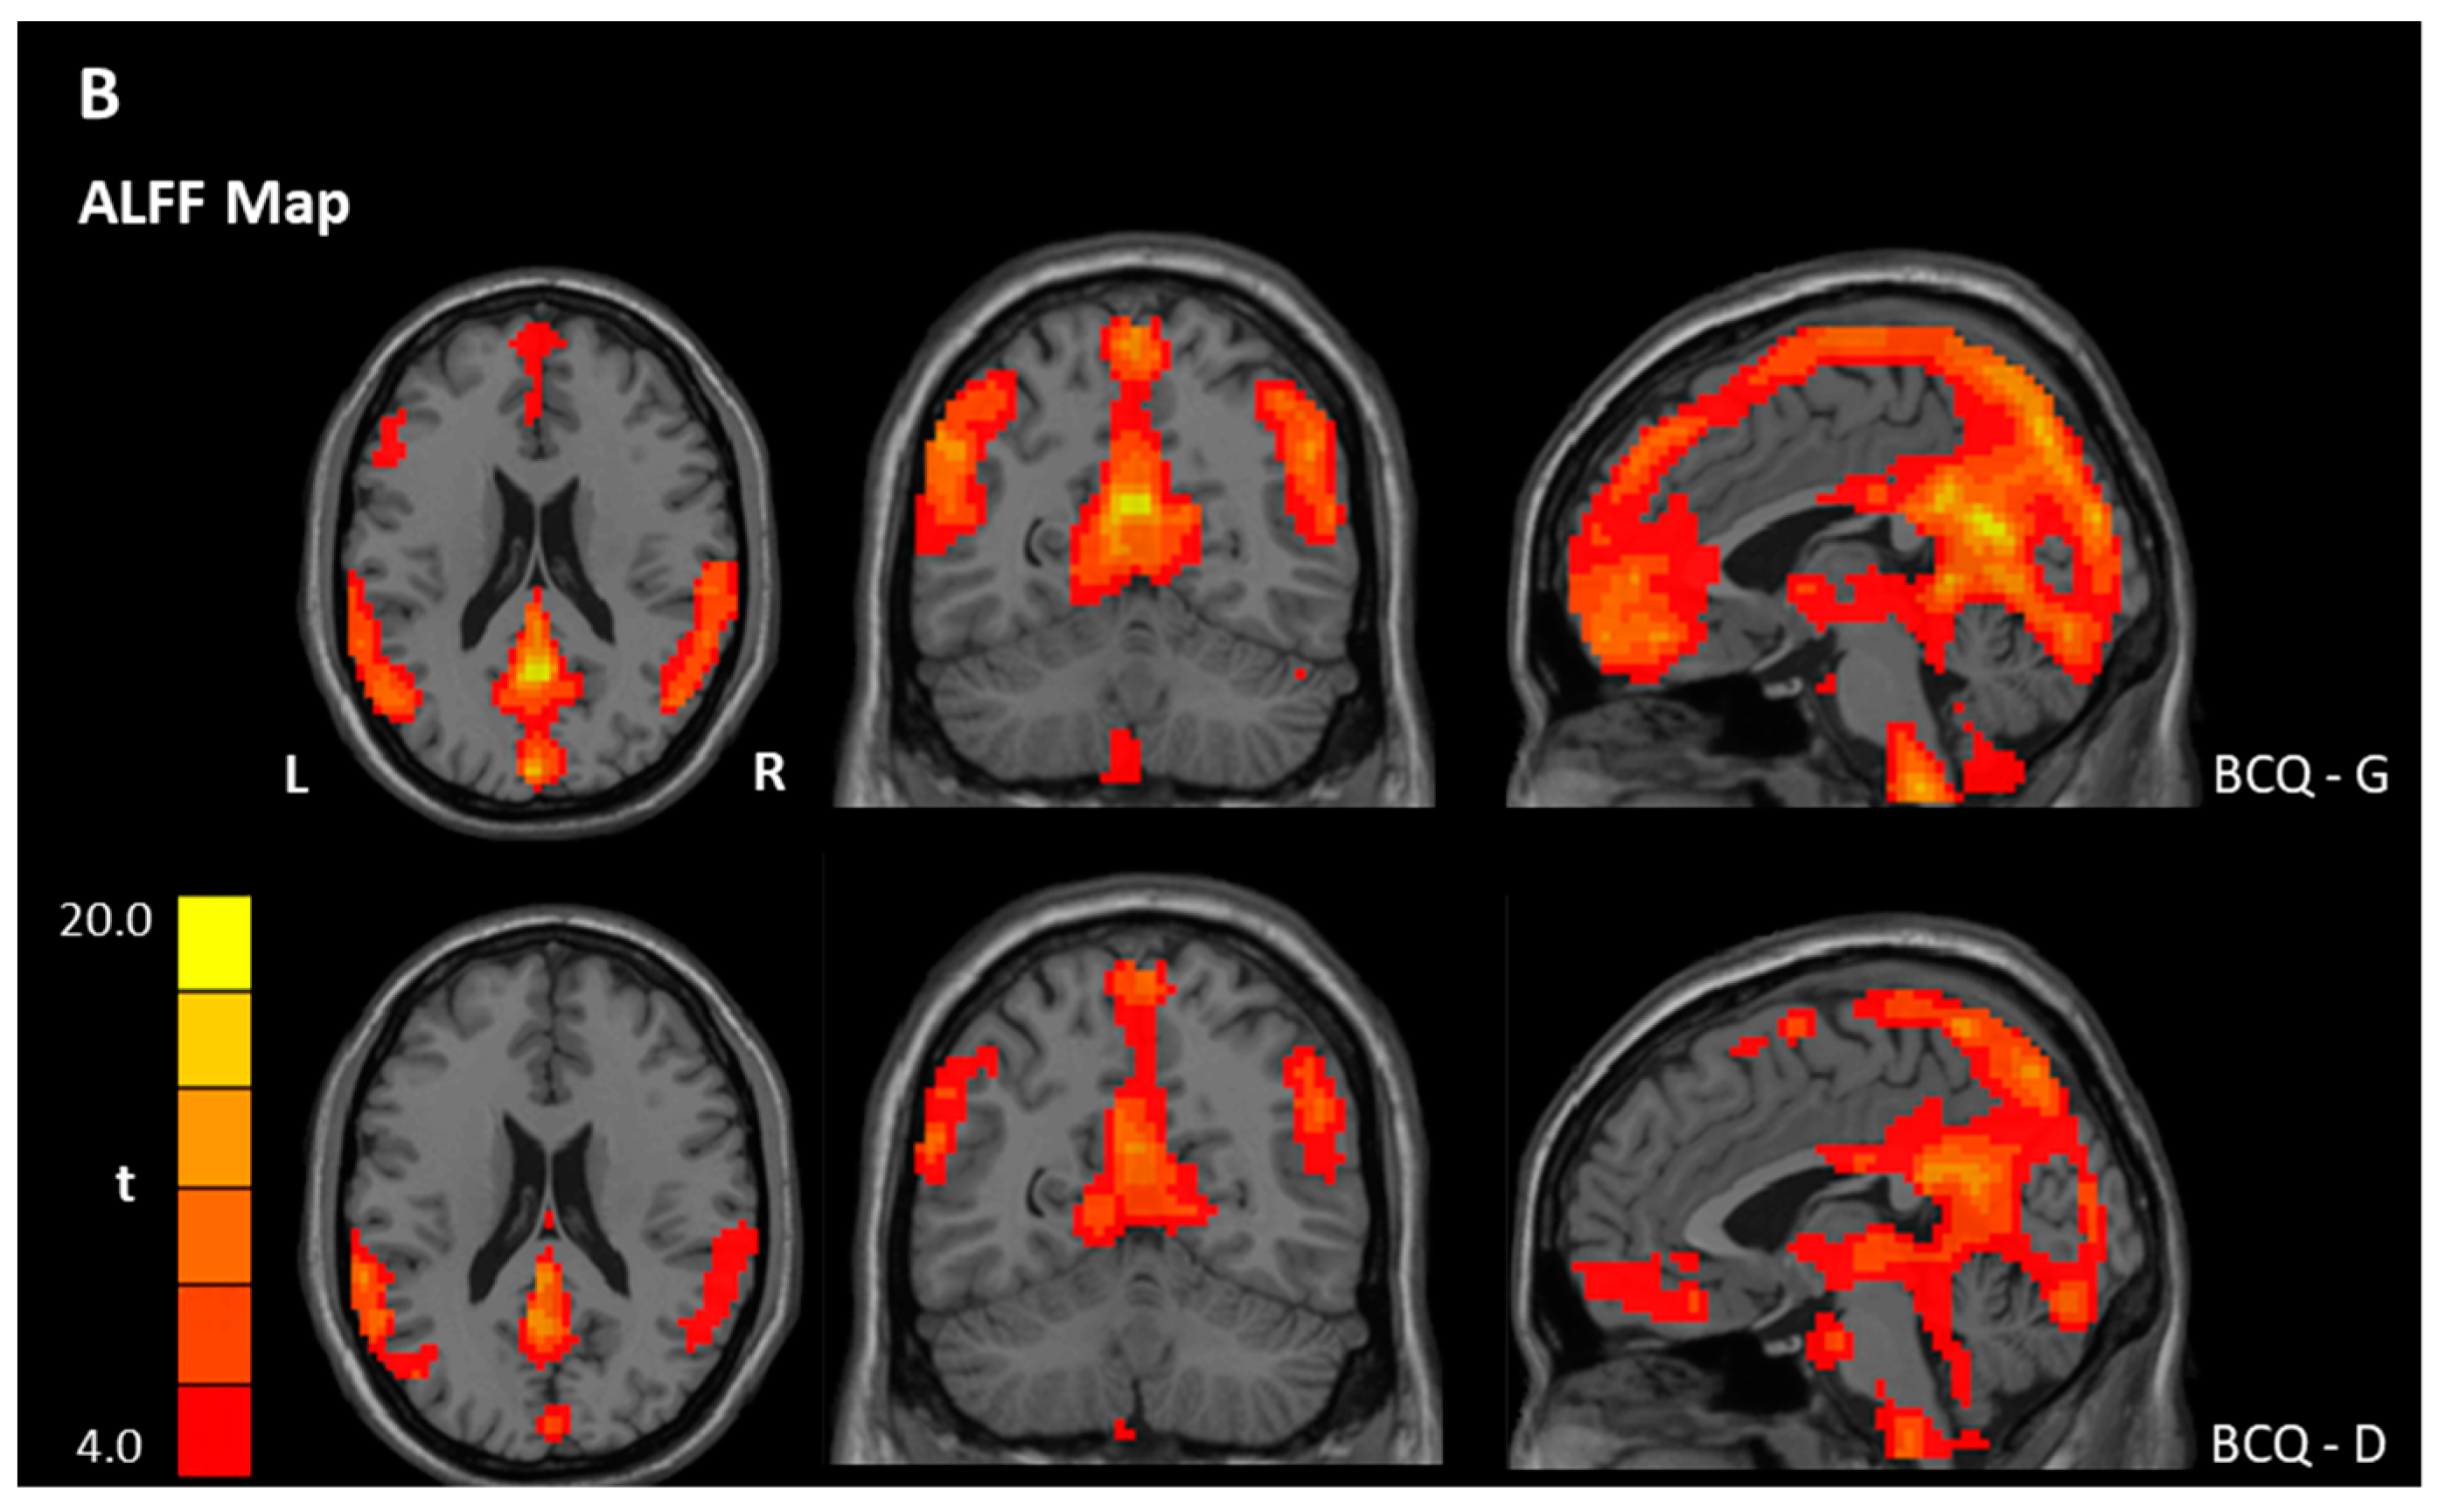

3.3. ReHo and ALFF Analyses

| Contrast | Region | BA | Size | t Score | Peak Coordinate | ||

|---|---|---|---|---|---|---|---|

| x | y | z | |||||

| ReHo | |||||||

| Within-group ** | |||||||

| BCQ-Gentleness | |||||||

| Gentleness > 0 | PCC, Left | 23 | 16,838 | 33.85 | −3 | −48 | 24 |

| Gentleness < 0 | NS | ||||||

| BCQ-Deficiency | |||||||

| Deficiency > 0 | PCC, Left | 23 | 8516 | 30.36 | −3 | −54 | 30 |

| OFC, Right | 11 | 4593 | 21.54 | 42 | 52 | −12 | |

| Deficiency < 0 | NS | ||||||

| Between-group * | |||||||

| Gentleness > Deficiency | Postcentral gyrus | 2 | 69 | 5.37 | 51 | −24 | 45 |

| Gentleness < Deficiency | NS | ||||||

| ALFF | |||||||

| Gentleness > 0 | PCC | 23 | 11639 | 17.34 | −3 | −54 | 21 |

| Deficiency > 0 | OFC, Left | 11 | 161 | 6.79 | −33 | 33 | −18 |

| Deficiency < 0 | Precentral gyrus, Left | 6 | 29,955 | 52.63 | −18 | −18 | 54 |

| Gentleness > Deficiency | NS | ||||||

| Gentleness < Deficiency | Pons/Cerebellum, Left | 85 | −3.86 | −12 | −36 | −54 | |